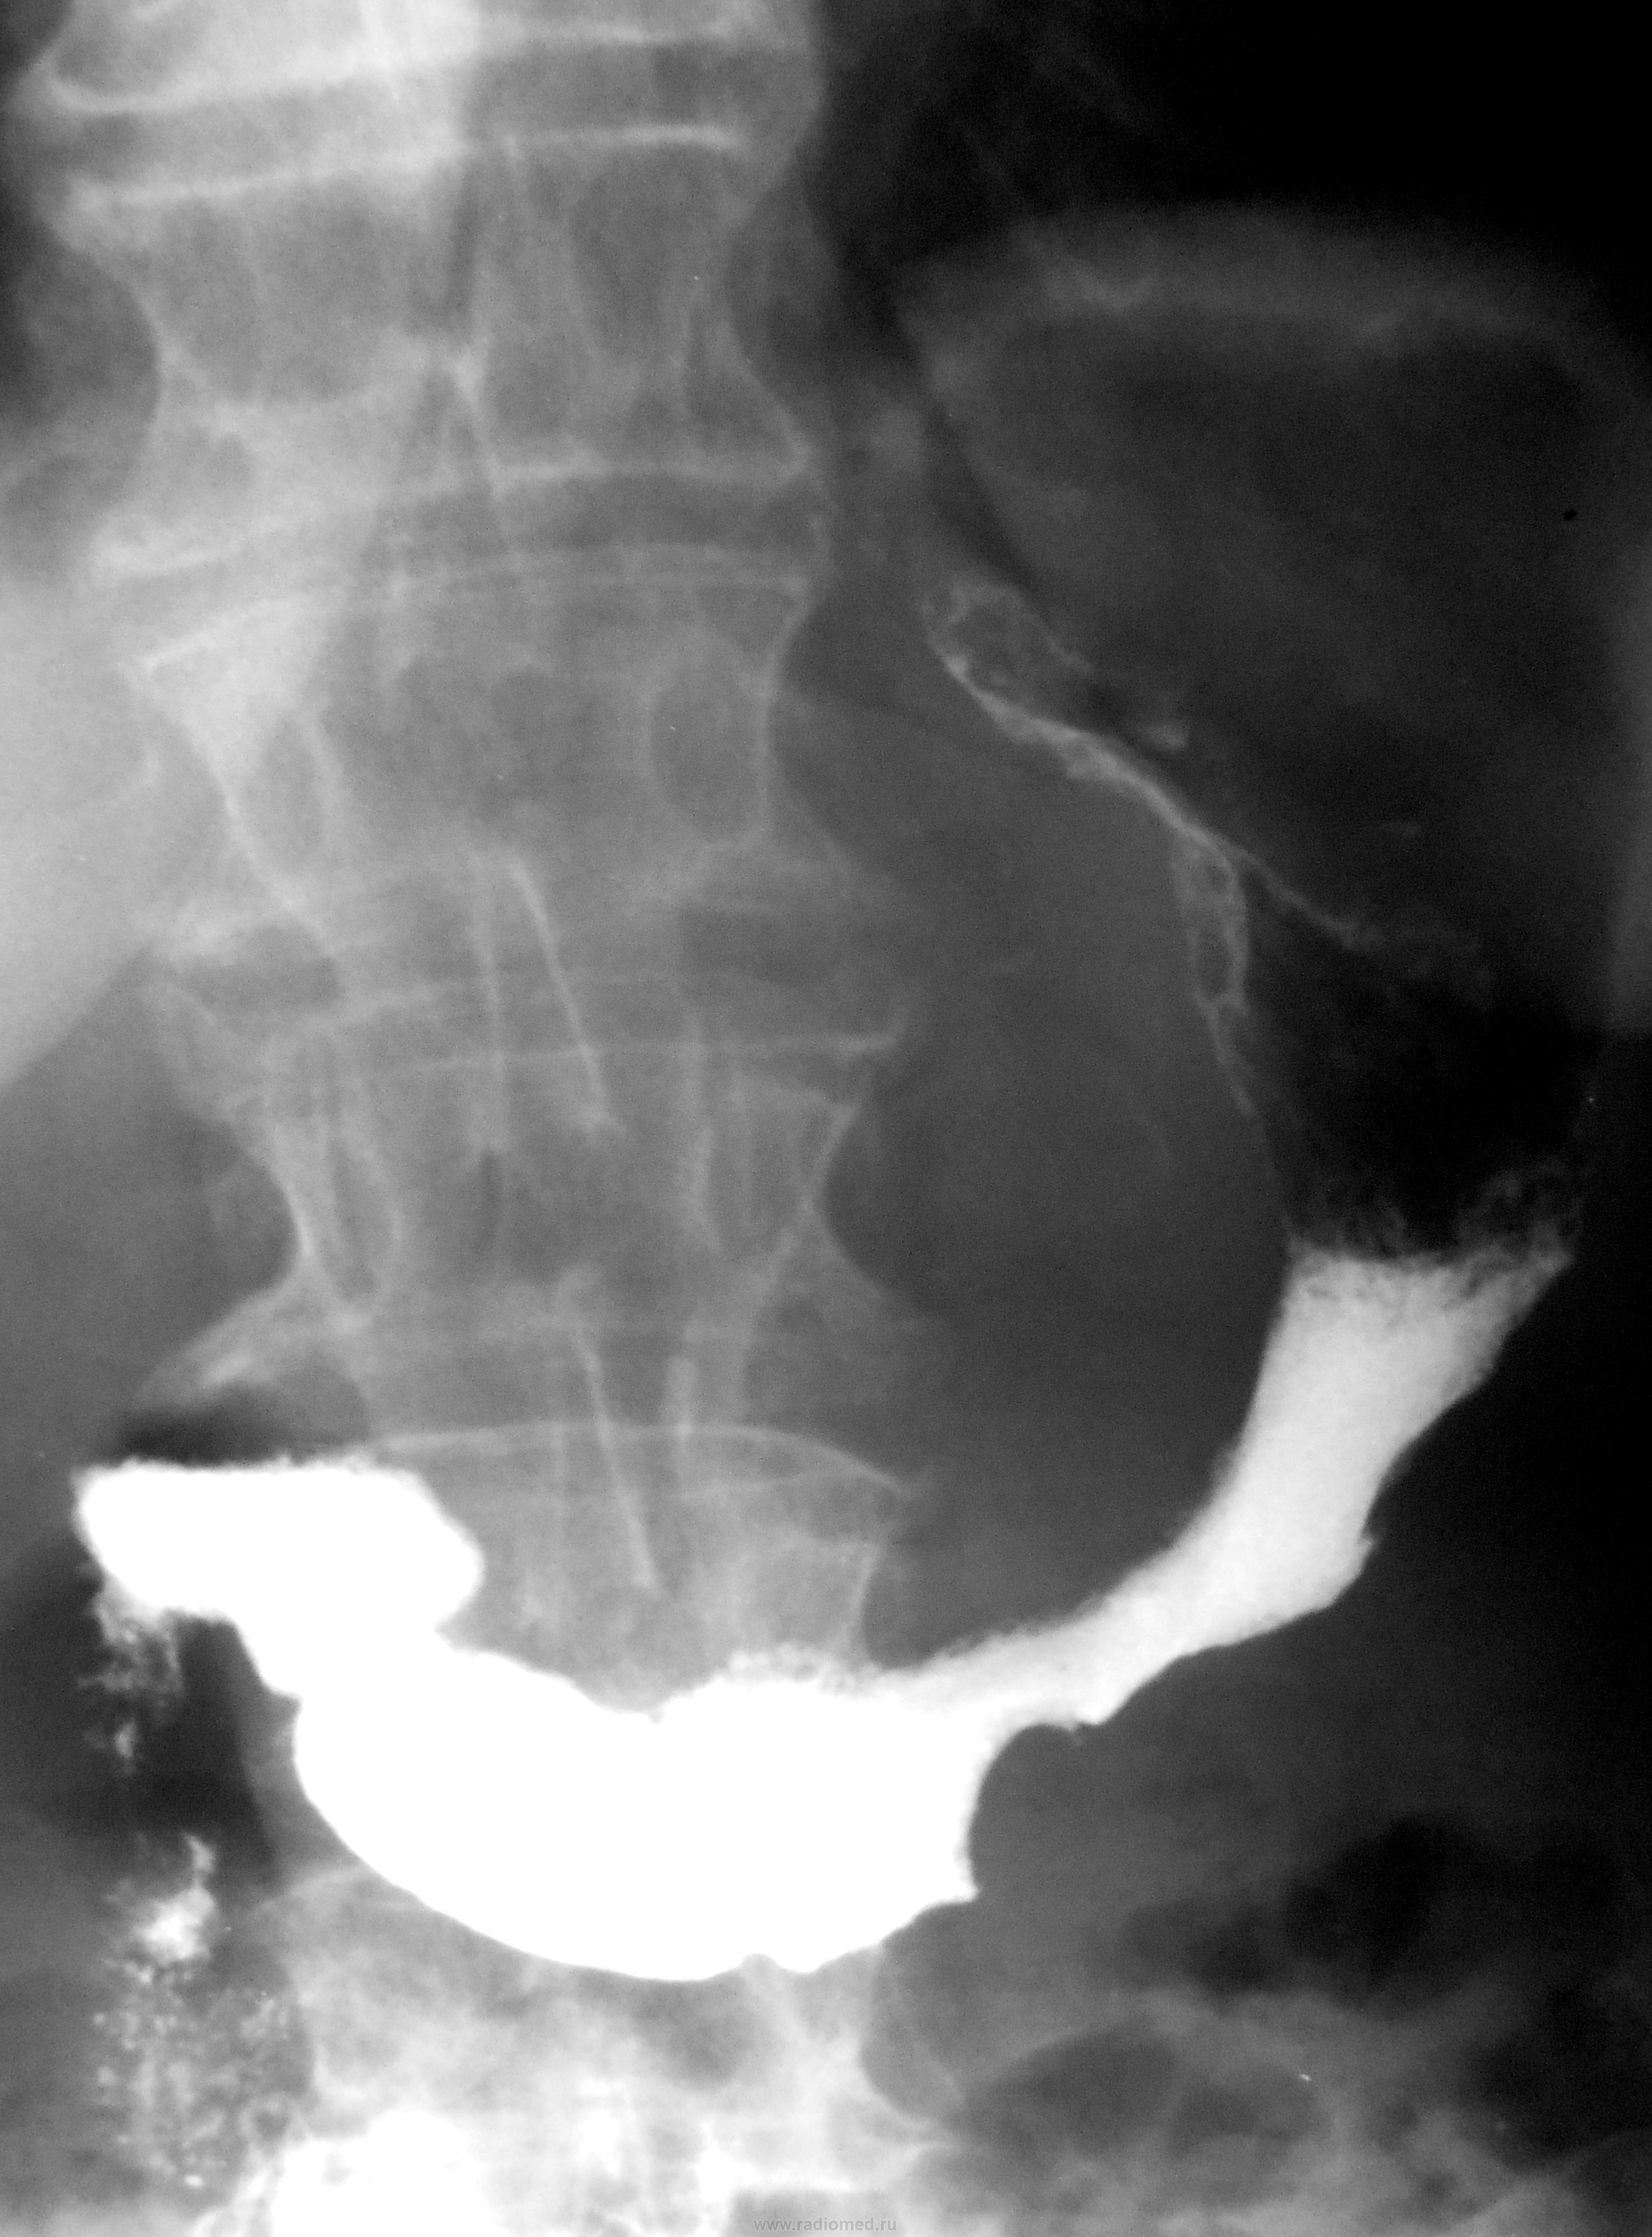

Судя по-всему, поражены отделы от субкардии до антрального.

+ еще дивертикул 12-типерстной кишки.

Конечно, на дивертикул можно было и сделать серию, но в данном, конкретном случае дивертикул не у дел..., при таком распространенном раковом поражении...

Но, отчасти Вы правы, ибо на рентгенологическое исследование пациентка была направлена с диагнозом...- "Дивертикул пищевода".